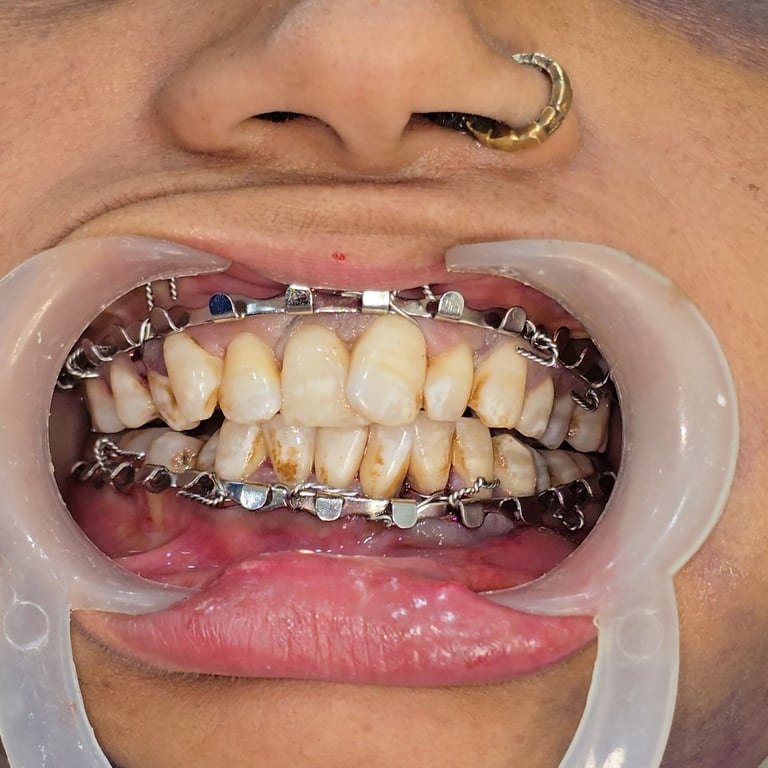

Facial trauma cases involving mandibular fractures are among the most common maxillofacial emergencies seen in dental and surgical practice. A fractured jaw not only causes severe pain and swelling but also affects chewing, speech, and overall facial aesthetics. In this blog, we present a rare case of multiple mandibular fractures in a 40-year-old female patient, including angle fracture, parasymphysis fracture, condylar fracture, and coronoid fracture—all treated successfully with intermaxillary fixation (IMF) and plating.